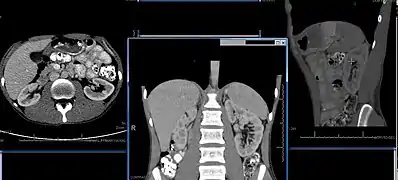

Normal adult right kidney as seen on abdominal ultrasound with a pole to pole measurement of 9.34 cm

Renal ultrasonography is essential in the diagnosis and management of kidney-related diseases.[44] Other modalities, such as CT and MRI, should always be considered as supplementary imaging modalities in the assessment of renal disease.[44]